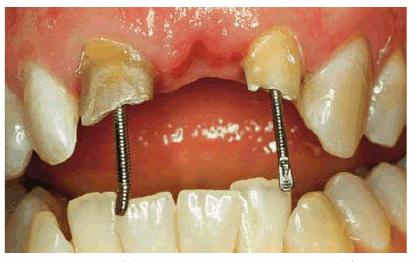

on both teeth (Figur 323s1823d es 18-7A

and B), the

patient returned to the general practitioner, who consulted the pediatric

dentist. The two agreed that someone skilled in cosmetic restorative procedures

should be called on for the reconstruction.

Figur 323s1823d e 18-7A and B: Although this 12-year-old girl was referred to an oral surgeon for a postaccident extraction of both fractured central incisors, he wisely referred the patient to an endodontist in an attempt to save the teeth.

TREATMENT: Because saving teeth was a step-by-step procedure involving

endodontic treatment, periodontal surgery, and reconstructive techniques, the

treatment plan could be changed if one of the suggested treatments failed.

Endodontic therapy had already been completed on both central incisors. These

surgical procedures were performed next: removal of the tooth fragments that

were fractured vertically, labial and lingual gingivectomy and gingivoplasty,

palatal ostectomy, and labial frenectomy (Figur 323s1823d e 18-7C). Approximately 5 mm of palatal

plate was removed to expose new margins on the fractured teeth (Figur 323s1823d e 18-7D). After the tissue healed, gold

posts were constructed and cemented on the two maxillary incisors (Figur 323s1823d es 18-7E to

H). Final

preparations were made, and impressions for aluminous porcelain crowns were

made. The two crowns were seated (Figur 323s1823d es 18-7I

and J Figur 323s1823d e 18-7K is a radiograph of the teeth at the

end of treatment.

Figur 323s1823d e 18-7C and D: Following endodontic therapy and removal of the fractured tooth fragments, periodontal surgery to lengthen the exposed crowns was performed.

Figur 323s1823d e 18-7E to H: Next, two posts and cores were constructed for the endodontically treated teeth.